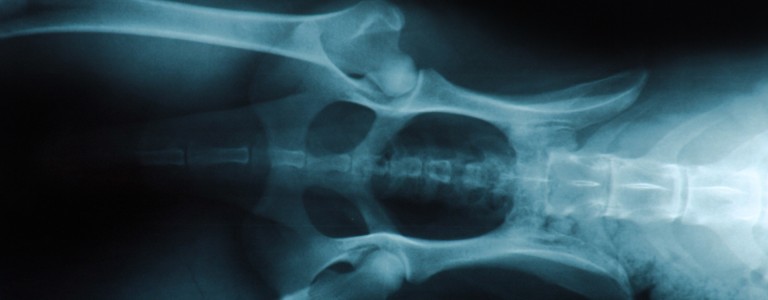

Si vous suspectez que votre chien souffre d'arthrose, un vétérinaire pourra en confirmer le diagnostic grâce à votre description des symptômes, un examen clinique complet et des examens d’imagerie.

En fonction de la cause initiale de la maladie, une chirurgie peut être envisagée, notamment dans le cas de dysplasie de la hanche